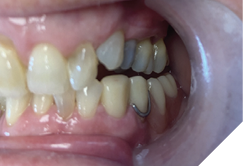

A 72-year-old Caucasian female presented with long-standing TMJ discomfort and missing teeth. She was diagnosed with partial mandibular edentulism (missing 37, 45, 46, 47), generalized attrition, and arthrogenic TMD due to posterior bite collapse. Her periodontal condition was stable.

After informed consent, Phase I began with delivery of a Gelb appliance (Fig. 3ABC), which was adjusted periodically until achieving the treatment VDO. Phase II involved stabilization at this VDO. Teeth 36, 35, 43, and 44 were prepared simultaneously, and impressions (Henry Schein VP MIX) and bite registration (Kopy ultra-fast VPS) were taken using the palatal jig.